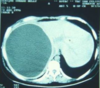

CXR

CT - eg water-lilly sign

US - Snowflake sign

-Either see Single cyst or with daughter cysts

ELISA for IgG (sensitive but not specific)

Western blot